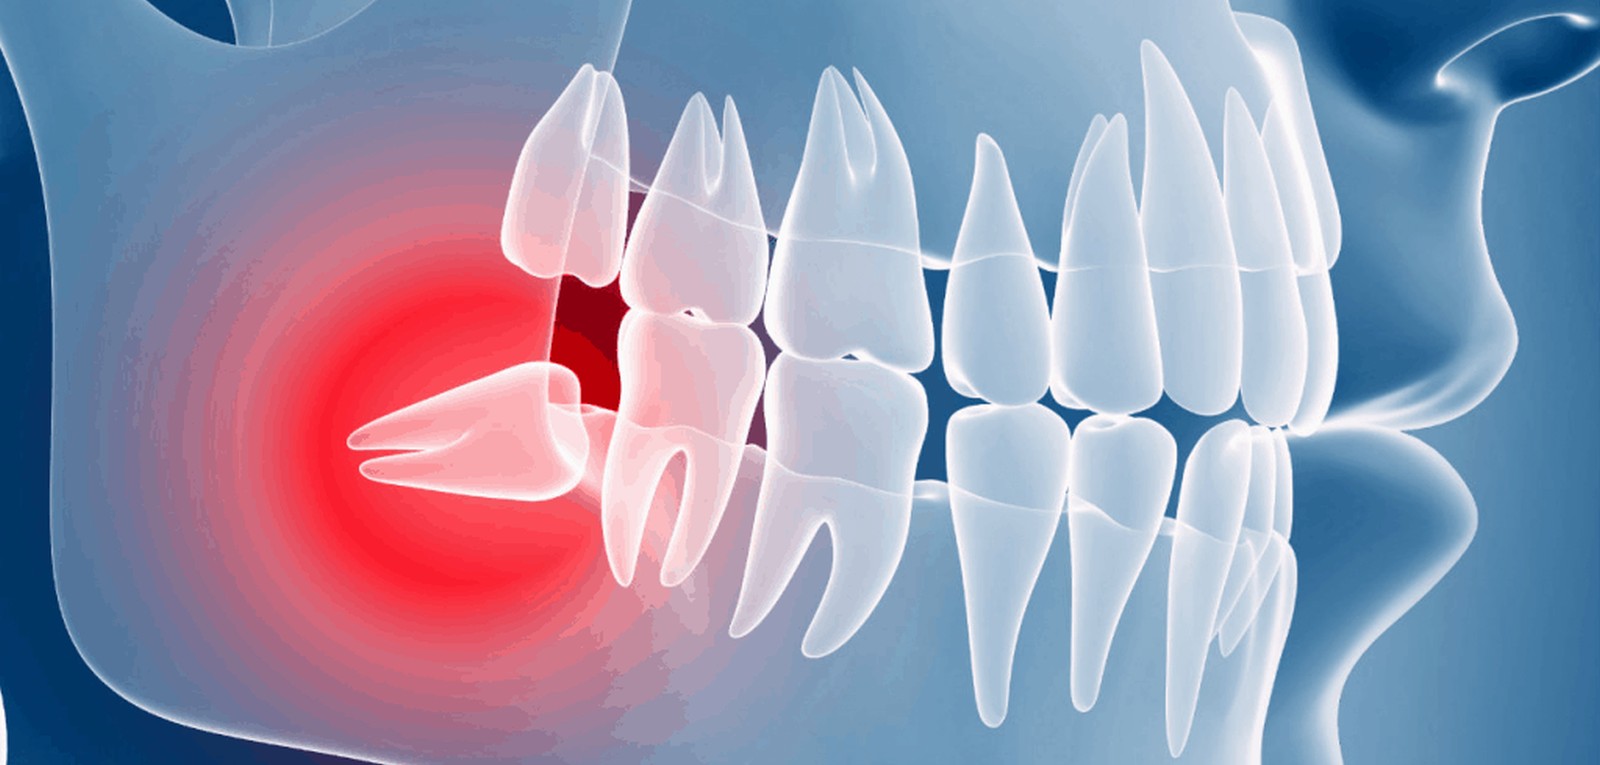

They can get partially stuck in your gums or grow at an angle. This is called an impacted wisdom tooth. Even impacted wisdom teeth don’t always need to be taken out if they aren’t causing any symptoms.

Sometimes though, the way an impacted wisdom tooth is positioned can make it easy for food and bacteria to get trapped around the gum. This can lead to swollen and sore gums (pericoronitis), tooth decay and infection. If you’re having problems such as these, your dentist may recommend taking the impacted tooth out.

Sometimes, your wisdom teeth don’t come through properly, meaning they’re impacted. This can cause problems such as pain, swelling and infection. Having your wisdom teeth taken out can ease these symptoms.